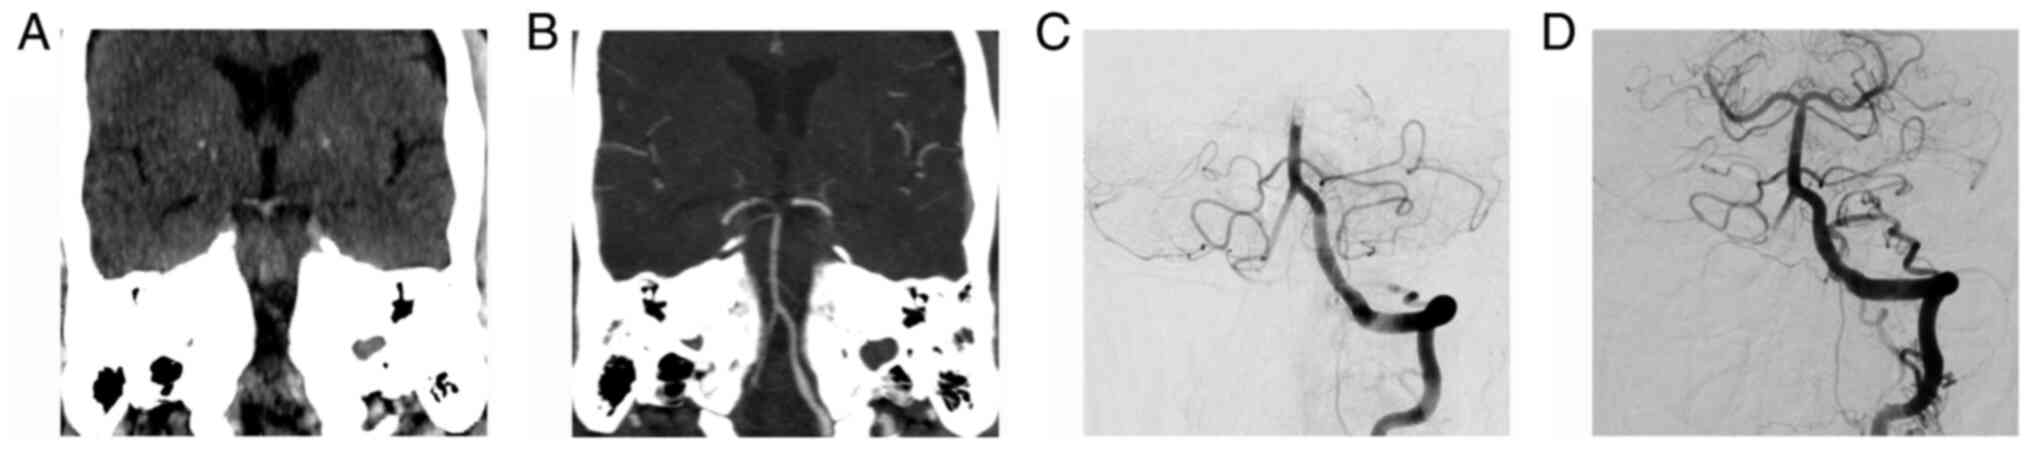

A hyperdense vessel is seen as a region of high attenuation on NCCT scans (Fig. 1). Pathologically it represents, in the appropriate clinical setting, an acute thrombus within the artery. The hyperdense appearance of fresh intravascular clots is determined by the extravasation of serum out of the clot, followed by a relative increase in concentration of red blood cells. Higher densities are mainly caused by the protein fraction of hemoglobin, much less by its iron content, which contributes only to 7-8% to its attenuation (10). Thrombi retrieved from patients with a dense MCA have, on average, a higher content of red blood cells (11-14) and are more frequently associated with a cardioembolic stroke subtype (15). These observations are not confirmed for BAO.

Figure 1

(A and B) Coronal reformated NCCT and CTA images reveal the HDBA sign and the corresponding distal BA thrombus, extending in both posterior cerebral arteries. (C and D) Before and after aspiration thrombectomy: Frontal projection digital subtraction angiography images confirm the BA occlusion, and subsequent recanalization. NCCT, non-contrast computer tomography; CTA, computer tomography angiography; HDBA, hyperdense basilar artery; BA, basilar artery.

The HDBA sign can be a useful tool for the detection of BAO, with a sensitivity ranging between 68 and 94% and a specificity between 80 and 98% (16-18). Sensitivity is higher if the clinical diagnosis of BAO is highly probable (14) or if the attenuation of the hyperdense vessel is measured. Optimal measured cut-off values that best discriminate a HDBA, range between 40 and 46 HU (17,18). Another method by which to increase detection of an HDBA, that was confirmed for dense MCAs, is to obtain a CT slice thickness of less than 2 mm or more appropriate 1 mm, and to view them on 5-mm-thick maximum intensity projection (MIP) reconstructions (19). One possible limitation of early studies evaluating the diagnostic value of the HDBA sign, is the use of a larger slice thickness, of 2 mm (16) or 4-5 mm (16,17), respectively. It is well known that a larger slice thickness increases partial volume averaging with cerebrospinal fluid and adjacent brain parenchyma, and can lead to false-negative NCCT results, potentially missing more hyperdense clots (18).

A dense basilar artery basilar artery (BA) sign is also valuable as a prognostic marker. It correlates well with discharge NIHSS and can independently predict short- (OR, 5.5; 95% CI, 2.2-13.6; P<0.001) (20) and long-term outcome (OR, 5.3; 95% CI, 1.1-33.3; P=0.05) (16). Nevertheless, in the absence of the HDBA sign, a brainstem ischemia or LVO should not be excluded; further contrast-enhanced vessel imaging is mandatory for the correct radiologic evaluation of patients with suspected posterior circulation stroke.